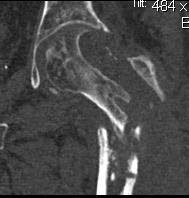

Re: Несращение проксимального отедла бедра, дефект головки

Вот еще снимки после и КТ.

Re: Несращение

кт